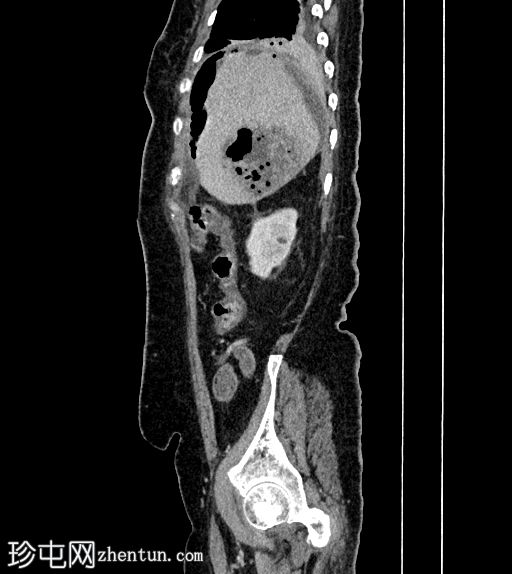

矢状位增强(C+)门静脉期

静脉期

8.jpg

肝段 6 和 7 可见多房性积液,呈环状强化

积液内可见多个气体腔

破入肝包膜下间隙,可见肝包膜下积液及气体腔

壁层腹膜与前腹壁之间可见另一局灶性积液

肝段 7 的肝内胆管局灶性扩张(0.3cm),内含气体腔

其他肝内胆管和肝外胆管均正常

胆囊缺失,可能由于既往胆囊切除术所致

无游离液体。

双侧肾皮质囊肿

轻度右侧胸腔积液伴邻近肺不张